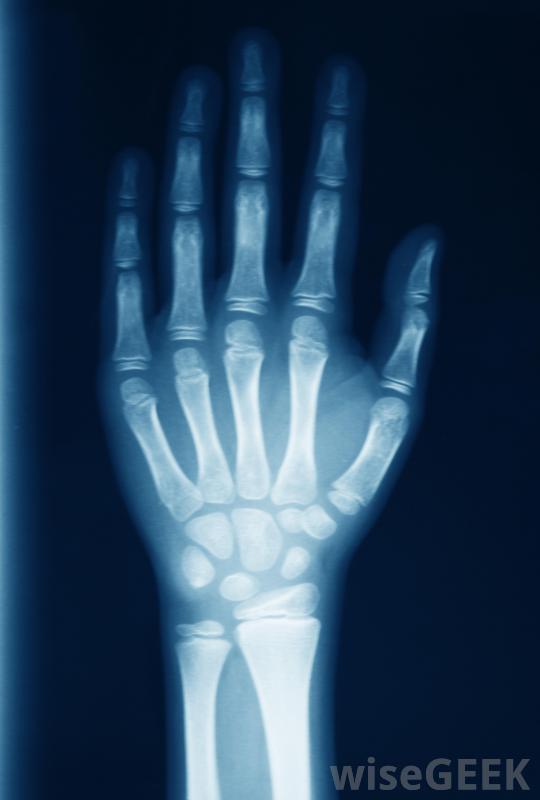

什么是手腕骨折(Wrist Fracture)?

骨折是指骨頭上的骨折,通常伴有皮膚、神經、血管和肌肉等軟組織的損傷。腕部骨折或腕部骨折是構成腕部的任何一根腕骨的骨折。骨折,包括手腕骨折,在嚴重程度、大小和正確愈合所需的治療類型。從臺階上摔下來會導致手腕骨折醫生可以將手腕骨折或其他骨折分為開放性骨折和閉合性骨折,也可以根據骨折的方式進行分類。例如,開放性腕關節骨折是指皮膚裂開,骨頭和其他軟組織可能會突出,并伴有出血。閉合性骨折是指皮膚沒有裂開的損傷,但是閉合性腕關節骨折并不一定比開放性骨折疼痛輕,開放性骨折和閉合性腕關節骨折最顯著的區別之一是,開放性骨折增加了患者發生嚴重感染的風險,并且始終需要手術才能正常愈合,閉合性骨折可能不需要手術治療。x光可以用來診斷手腕骨折"粉碎的"、"綠色的"和"成角度的"這些術語被醫學專業人士用來指骨頭斷裂的方式。如果手腕骨折涉及到腕關節多處骨折,它可以被稱為粉碎性骨折。其中一塊骨頭的不完全斷裂可以被稱為綠枝骨折。成角這個術語是指以一定角度斷裂的骨頭,主要用于描述長骨的骨折,如手臂的骨折,而不是形成手腕的不規則形狀的腕骨腕部骨折是指骨頭斷裂,也可能伴有周圍軟組織(如皮膚和肌肉)的損傷雖然用X光片或其他影像學方法來確認是否真的發生了腕關節骨折,但如果該部位疼痛、腫脹或有任何畸形跡象,則應高度懷疑這種損傷。尤其是當患者的其他部位受到嚴重創傷時他或她的身體。除了通過開放性骨折突出的骨頭外,腕關節畸形可能是腕骨骨折最準確的標志之一。腕部骨折的嚴重程度、治療方式和愈合所需的時間有很大的不同腕部骨折是最常見的骨折。手腕骨折應由醫生治療手腕外傷可能使橈動脈搏動難以定位。